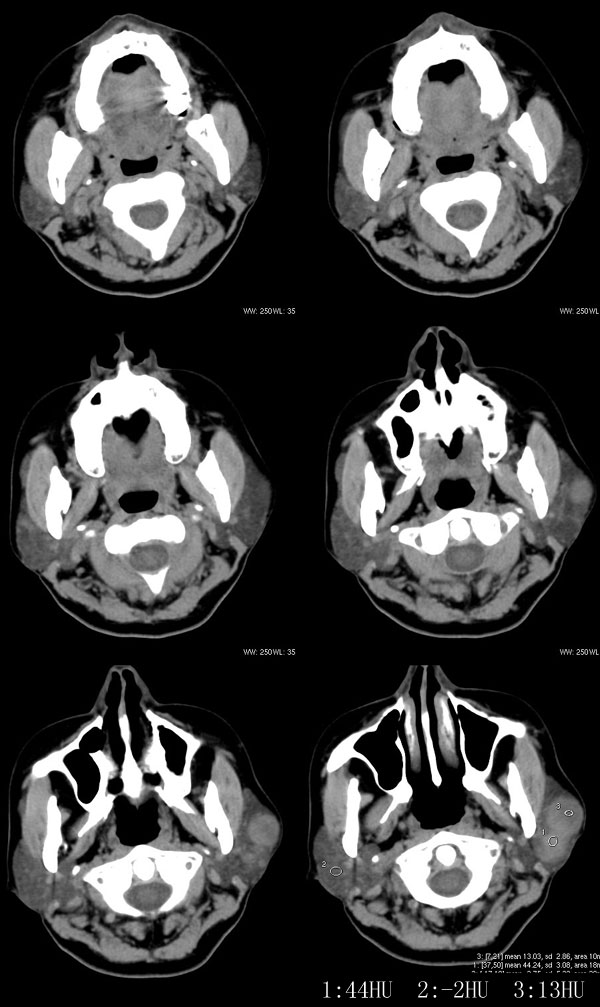

女性,43岁。左腮部肿物5年。体检:(肿物)质中,约5x4x4cm,边界清,固定。

左腮腺肿物,内可见低密度坏死区,增强扫描示肿块明显强化,且呈持续延迟强化,常规考虑腮混合瘤可能性大,但强化表现不太符合,不除外腮腺纤维血管瘤、神经鞘瘤、淋巴瘤及巨淋巴结增生症

考虑左侧腮腺混合瘤。  肿瘤较大,边清,囊变,强化明显,皮肤及淋巴结无异示

左侧腮腺多形性腺瘤可能性大。1、是混合瘤中最常见的良性肿瘤;2、中年女性多见并且时间长症状轻;3、病灶内有低密度坏死区,增强时强化;4、其内有钙化,囊性部分未强化;5、需与囊性淋巴瘤相鉴别。